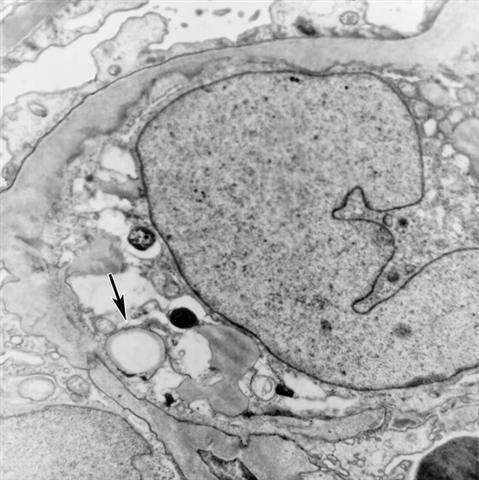

Рис. 6в). Электронограмма почки при фокальном сегментарном гломерулярном гиалинозе — в цитоплазме мезангиальных клеток содержатся липиды, указано стрелкой; ´12000.